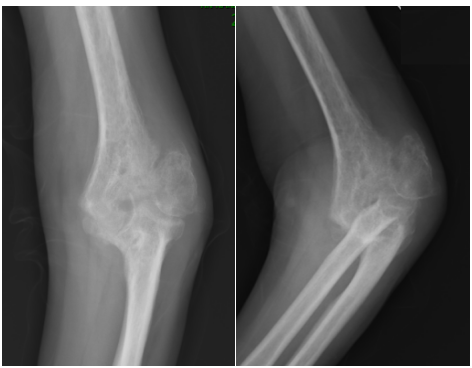

骨科主任陈志伟接诊了赵阿姨并仔细查看其X片发现:左肘关节皮质不连续,伴随明显骨质增生影、关节间隙严重变窄。诊断为:左肱骨外髁陈旧性骨折并肘关节创伤性关节炎。考虑到赵阿姨关节膨大畸形伴僵硬,屈伸活动仅10°左右,且伴有局部长期疼痛,甚至严重影响睡眠质量,经保守治疗效果不佳,建议赵阿姨住院进行手术治疗。

患者术前影像学检查资料